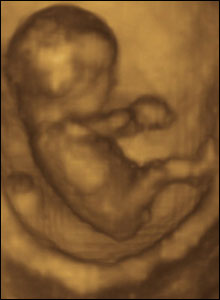

Abortionist Dr. Joseph Randall:

“I think the greatest thing that got to us was the ultrasound. At that time, the ultrasound, or soundwave picture which was moving, called a “real-time ultrasound,” showed the baby on TV. The baby really came alive on TV and was moving. And that picture, that picture of the baby on ultrasound bothered me more than anything else… We lost two nurses. They couldn’t take looking at.”